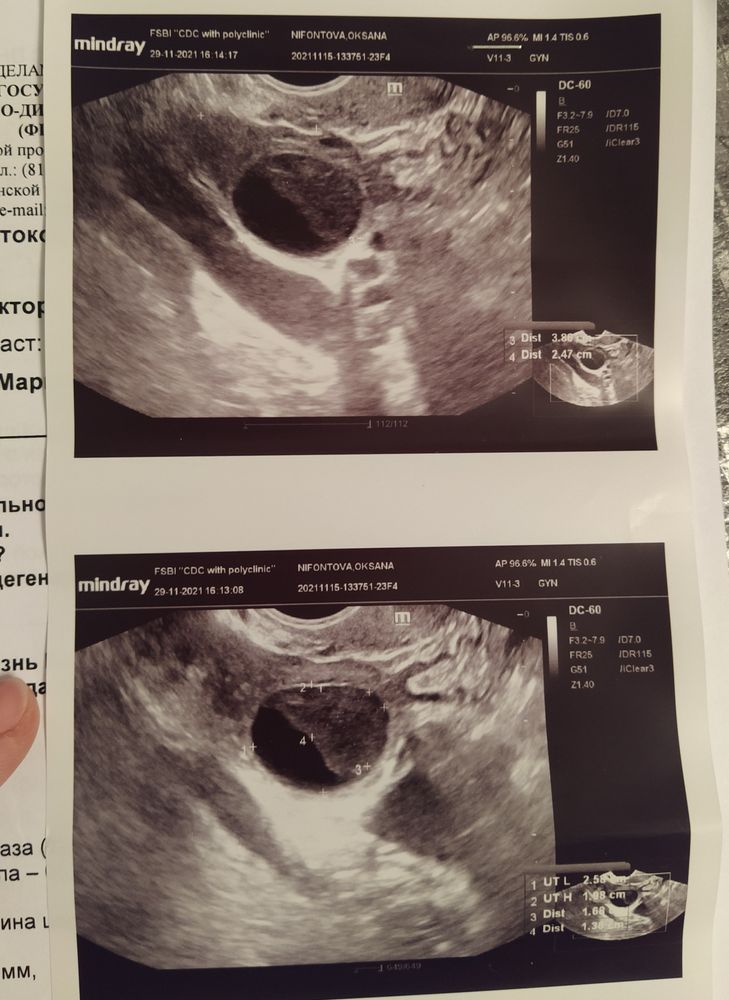

Сегодня 25 дц. Свой цикл 24-28 дней. Если бы не УЗИ, я бы подумала, что на 10 дпо БТ 36,7 указывает на ИЗ, или начала снижаться к М. Но судя по 2м предыдущим УЗИ на 11 и на 18 дц - овуляции не было. А почему БТ поднялась - ХЗ. Тестами на овуляцию всегда ловлю ее. За год 2 раза была на УЗИ, и каждый раз говорили, что ЖТ есть - один раз нормальное, второй раз очень маленькое....

Сегодня на УЗИ врач была удивлена не меньше моего

Так и не смогла она мне ответить - фоллик это или что. На 18 дц он был 20,8мм. На 21 дц прогик сдавала - 9,03 нг/мл. В анамнезе низкий АМГ (0,53-0,8).

Сказала, что по УЗИ не намека на приближение М, поэтому предлагает вызывать их дюфастоном, но почему-то аж на 12 дней принимать его.